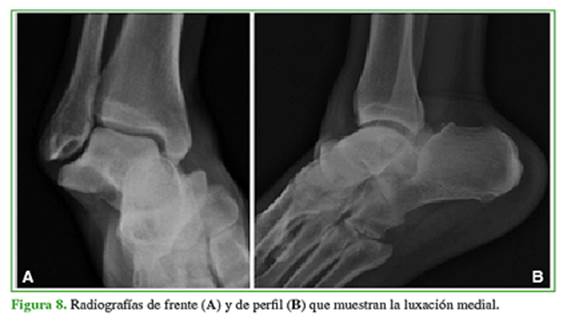

Hombre de 44 años que sufrió un traumatismo de tobillo durante una actividad deportiva. Fue traído en ambulancia a nuestra central de emergencias, a las 6 h del traumatismo. Tenía dolor, deformidad e impotencia funcional del tobillo derecho. Las radiografías mostraron una incongruencia articular con luxación periastragalina medial (Figura 8).